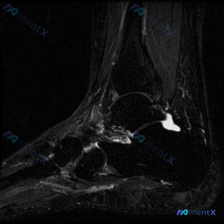

踝关节MRI读片病例分享,整理了完整分析思路 这是一例踝关节矢状位T2加权MRI,我把影像发现和分析思路整理出来,和大家一起讨论。 一、基本影像信息 这是踝关节MRI T2序列矢状位图像,可观察到胫骨远端、距骨、跟骨及周围软组织结构,核心阳性征象如下: 1. 骨骼关节改变:距骨穹窿(圆顶)可见明确局...

看到这个踝关节MRI的读片请求,问题是观察到的软组织积液,我整理了完整的影像和分析思路分享给大家。 病例影像基础信息 这是踝关节MRI矢状位T2序列图像,核心观察结果如下: 1. 骨骼系统:胫骨远端、距骨、跟骨、舟骨骨皮质完整,未见明确骨折线;距骨体及跟骨骨髓信号均匀,无明显水肿或硬化改变 2. 关...

今天给大家分享一张踝关节MRI矢状位T2加权影像的读片分析,病例本身并不复杂,但这种仅表现为少量积液的情况,临床其实很容易走偏,整理一下完整的思考过程给大家参考。 一、影像核心信息整理 这张是踝关节矢状位T2加权MRI,我们先把所有明确的影像信息理清楚: 1. 骨骼结构:胫骨远端、距骨、跟骨、舟骨骨...

看到一份很有代表性的踝关节MRI影像,整理了资料和分析思路分享给大家。 病例影像基本信息 这是一份踝关节矢状位T2加权像(T2WI),先给大家说下客观观察到的结果: 1. 解剖结构显示清晰:可以看到胫骨远端、距骨、跟骨、足舟骨及部分跖骨 2. 核心异常发现: - 胫距关节腔前方、后方可见明显T2高信...

最近看到这例踝关节MRI读片讨论,问题是「图像中能观察到什么软组织液相关改变」,整理一下完整分析思路,分享给大家。 一、病例影像核心信息 这是踝关节MRI冠状位T2加权图像,核心发现如下: 1. 骨结构改变:胫骨远端、距骨、跟骨显影清晰,距骨穹窿内侧关节面可见局灶性高信号改变,边界清晰,呈楔形凹陷状...